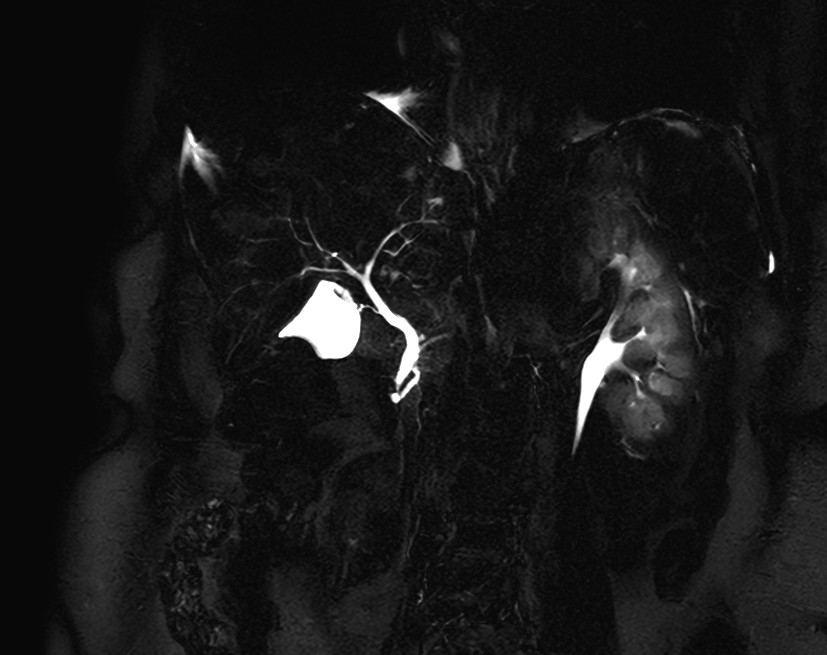

Coronal MRCP SSh

Axial MRCP 2D